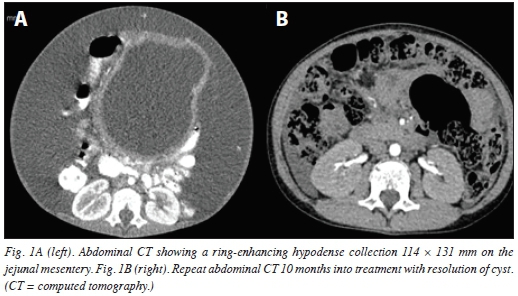

Complete blood count showed lymphocytosis of 15 χ 107L and erythrocyte sedimentation rate (ESR) of 30 mm/hr. Tuberculin skin test was negative. Ascitic fluid was exudative (protein of 9 g/dL), but acid-fast bacilli (AFB) and geneXpert tests of the fluid were negative. The child's HIV status was negative on 2 separate occasions during the course of the current illness. Chest radiograph showed consolidation of the left mid and lower zones. Abdominal ultrasound showed a rounded, thick-walled cystic lesion with clear contents, measuring 118 χ 132 mm around the epigastric area. Abdominal computed tomography (CT) confirmed the findings of a ring-enhancing hypodense collection 114 χ 131 mm on the jejunal mesentery (Fig. 1a).

Within 2 weeks, a diagnosis of disseminated TB (chest and abdomen) based on a high index of suspicion was made. The patient was immediately commenced on first-line treatment for TB (rifampicin, pyrazinamide, isoniazid, ethambutol), oral prednisolone for 6 weeks and nutritional rehabilitation. During the early course of treatment, the patient also had 4 abdominal paracenteses to relieve severe abdominal distension and respiratory distress. By the third month of treatment, the patient had improved with reduction in abdominal girth (57 cm, 11 cm from the tip of the xiphoid process), no fever, improved appetite, gained weight and no more respiratory distress. At 6 months, remarkable improvement was noted, with no abdominal distension. At 8 months, there was complete resolution of signs and symptoms, and a repeat abdominal CT scan showed normal findings (Fig. 1b). Other close family members were screened for TB, and the mother and younger sister were found to be positive for TB and commenced on treatment.